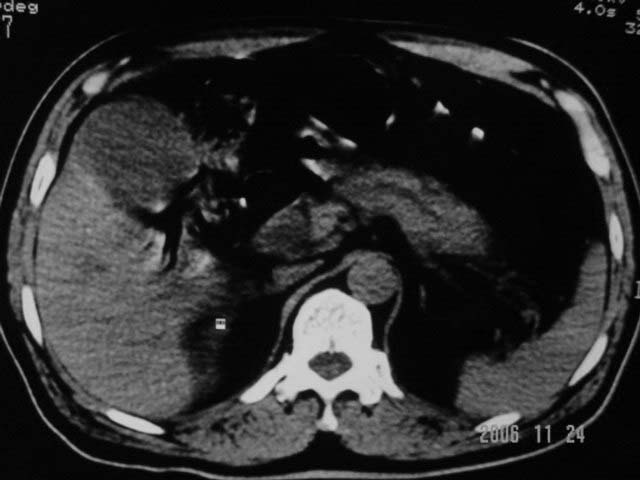

标题: CT5395:男、60岁,皮肤、巩膜黄染伴上腹部疼痛20天 [打印本页]

标题: CT5395:男、60岁,皮肤、巩膜黄染伴上腹部疼痛20天

劳烦各位老师看一下最后一幅箭头指的地方是不是胆总管结石.ct值约63hu.

感觉不是结石可能,与上一层面联系应该是门脉区影像,图像显示不佳,胆总管显示不清[特别是胰头以上段],目前影像只能说肝内外胆管扩张,胰管扩张,胆囊扩大。提示胆总管远端梗阻。可考虑肿瘤或结石所致

请结合临床及进一步检查。

肝内外胆管及胰管均示有扩张,胆囊增大.提示胆总管远端梗阻,可考虑肿瘤或结石或肿瘤伴结石,建议强化扫描